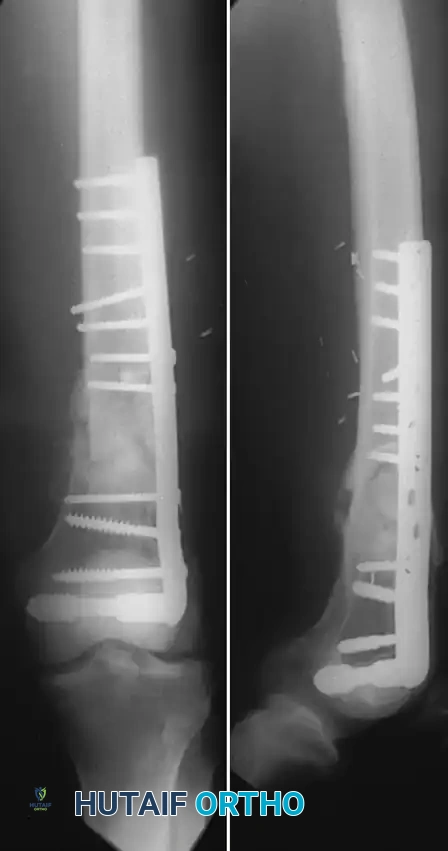

Condylar Buttress and Locked Plating Systems

For fractures with less than 3 to 4 cm of intact femoral condylar bone, or those with extensive articular comminution, traditional fixed-angle devices fail. Historically, the condylar buttress plate was utilized, allowing multiple screws to be directed into small comminuted fragments. However, without locking technology, fractures with medial comminution often collapsed into varus due to toggle at the screw-plate interface.

The Advent of Locked Plating:

The introduction of locking plate technology, specifically the Less Invasive Stabilization System (LISS) and modern Locking Compression Plates (LCP), revolutionized distal femur fracture management.

* Biomechanics: Locked screws thread directly into the plate, creating a fixed-angle construct that does not rely on friction between the plate and bone. This mitigates varus angulation even in the presence of a medial femoral defect, often eliminating the historical need for dual (medial and lateral) plating.

* Elastic Deformation: The LISS plate allows for higher elastic deformation than rigid DCS systems, acting as an internal fixator that promotes secondary bone healing via callus formation.

* Modern Implants: Newer locking implants feature polyaxial locking capabilities, allowing the surgeon to angle screws up to 15 degrees off-axis to capture specific articular fragments or avoid existing intramedullary stems in periprosthetic fractures.